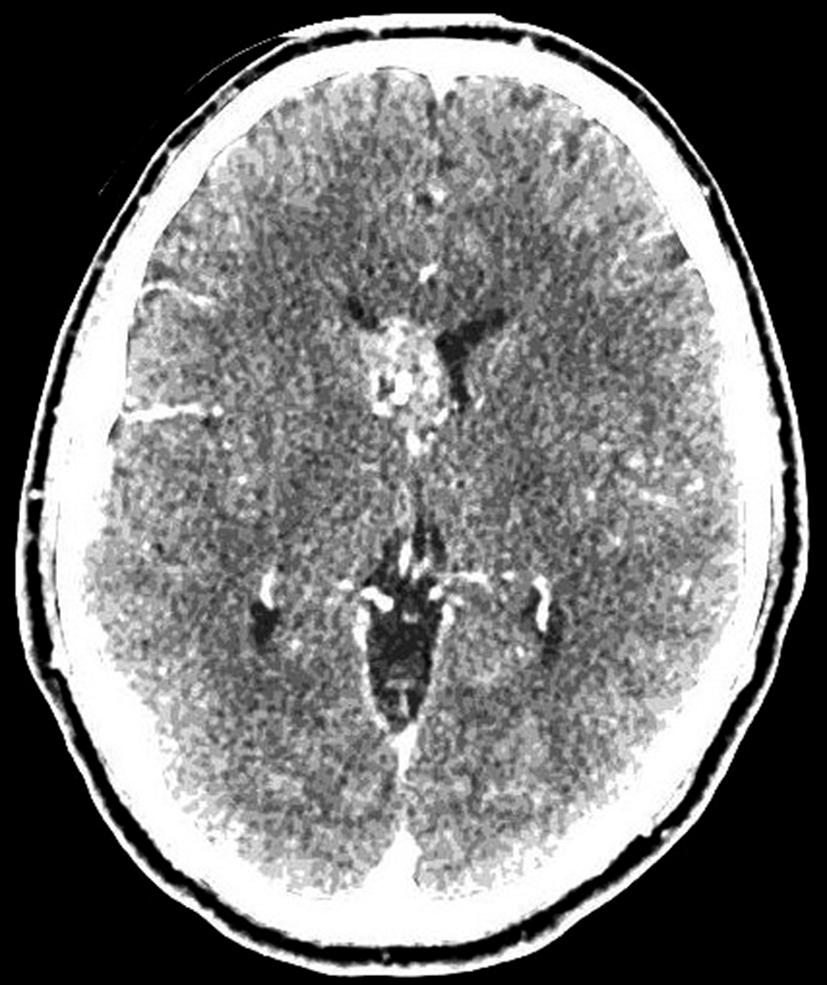

Se presenta el caso clínico de un paciente de sexo masculino, de 36 años de edad, sin antecedentes personales a destacar. Consulta por cefalea holocraneana de larga data, sin déficit neurológico y examen físico normal. Dada la clínica del paciente se realiza una tomografía computada de cráneo sin contraste intravenoso que identifica una lesión bien definida espontáneamente hiperdensa, heterogénea con calcificaciones puntiformes localizada en el asta frontal del ventrículo lateral derecho. No hay edema peri-lesional, efecto de masa ni hidrocefalia (Figura 1- A). Debido a los hallazgos se decide administrar contraste intravenoso, no evidenciándose realce significativo de la lesión (Figura 1- B).

a) TC sin contraste. Lesión intraventricular hiperdensa, heterogénea con pequeñas calcificaciones.

a) TC con contraste. No se identifica realce significativo de la lesión.

En la TC sin contraste, el cavernoma es una lesión bien definida e hiperdensa. El aumento de la densidad puede tener un aspecto punteado, que puede representar calcio, sangre o una combinación de ambos y el realce tras la administración de contraste varía de ninguno a muy intenso (1,3,5).